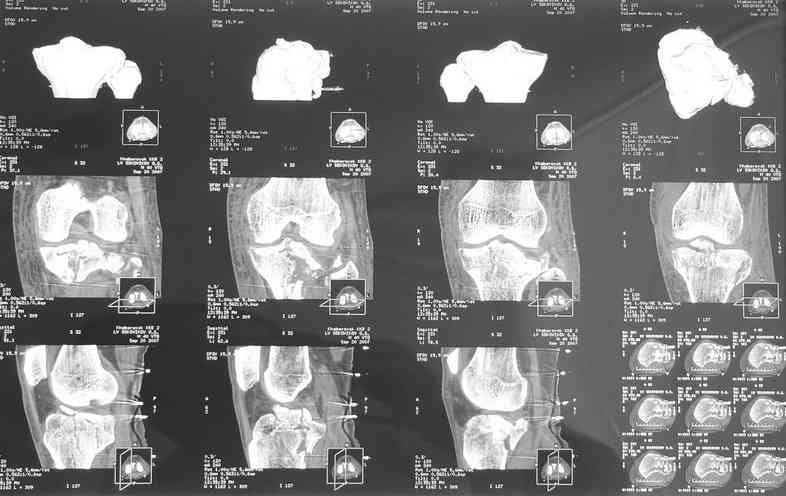

Коллеги здравствуйте! Прошу простить- техническая накладка. данные КТ в приложении. На лечении находится пациент 4о лет с многооскольчатым импрессионным межмыщелковым переломом голени. по данным КТ - отрыв межмыщелкового возвышения, преимущественно просела задняя часть наружного мыщелка, глубина импрессии порядка 2 см. какой доступ предпочтительнее, чем фиксировать?

Уважаемый Леонид! Вы имеете дело с переломом Tibial plateau. Для того, чтобы можно было классифицировать перелом, представленных снимков КТ не достаточно, поэтому, если можно дайте снимки рентгеновские обыкновенные.

Есть несколько классификаций переломов тибиального плато. Одна из них - классифокация Шацкера.

Скорее всего у Вашего пациента Бикондилярный перелом проксимальной тибии с депрессией латерального тибиального плато.